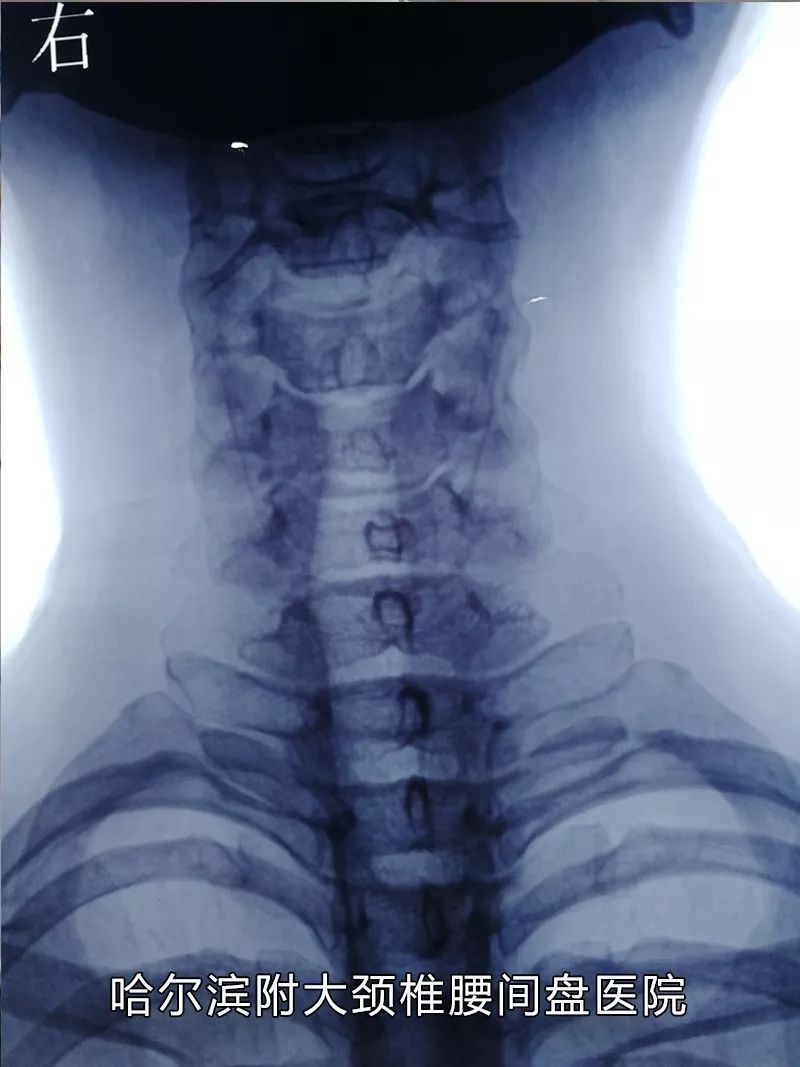

很多腰椎间盘突出患者也和老刘一样,发病时疼痛难忍,严重影响工作生活。但经过几天常规治疗后,病情慢慢恢复,疼痛逐步减轻了。于是,抱着侥幸心理:也许拖一拖就过去了,以后不再疼了。谁料想,没过多长时间,病情又复发了,而且一次比一次严重。哈尔滨附大颈椎腰间盘医院的刘达生院长告诫患者:腰椎病病情缓解后,一定要利用病情好转的契机,抓紧时间治疗,否则病情反复发作,后果不堪设想!

7月14日本周二做客《你好,医生!》的医生是:刘达生

刘达生

哈尔滨附大颈椎腰间盘医院业务院长、会诊中心主任

长期从事颈椎病、腰间盘突出、椎管狭窄等骨科疾病的治疗。